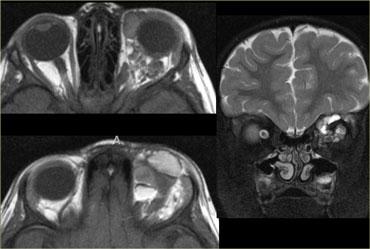

Trên hình bên trái, thần kinh thị giác bên phải có hình ảnh bình thường.

Lưu ý rằng thần kinh thị giác là một bó chất trắng.

Nó có cùng cường độ tín hiệu với chất trắng trong não.

Ở phía đối bên, thần kinh thị giác có tín hiệu tăng cao.

Đây là tổn thương ngoài nhãn cầu trong nón cơ, và chúng ta cần nghĩ đến các bệnh lý tân sinh so với bệnh lý mất myelin.

Tiếp tục xem hình ảnh tiếp theo.Bên trái là hình ảnh chuỗi xung FLAIR kết hợp kỹ thuật ức chế mỡ (fat-sat).

Lưu ý tín hiệu bất thường và thực tế là thần kinh thị giác không bị phì đại, điều này giúp loại trừ khả năng u.Hình ảnh tủy sống cổ cho thấy một đoạn dài tổn thương không chiếm chỗ.

Dựa trên các hình ảnh này, chẩn đoán phân biệt bao gồm xơ cứng rải rác (MS) và hội chứng Devic (còn gọi là viêm tủy thị thần kinh).

Do MS phổ biến hơn nhiều, đây sẽ là chẩn đoán có khả năng nhất, nhưng trường hợp này thực tế là hội chứng Devic.Một số tác giả coi hội chứng Devic là một thể của MS, tuy nhiên hội chứng Devic khác với MS ở các điểm sau: